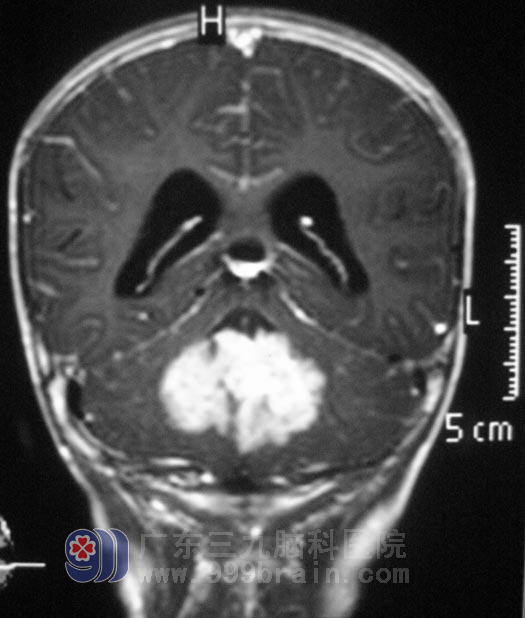

广东三九脑科医院MR检查提示病变范围约5.04cm×3.31cm×4.12cm,脑干受推压、前移,桥前池边窄,初步考虑髓母细胞瘤。

3月5日,由综合神经外科 鲁明主任主刀在全麻下行后正中入路四脑室占位病变切除术,术中显微镜下见肿瘤呈粉红色、质软,有钙化,血供丰富,边界清楚,沿肿瘤与延髓交界处向上分离,予肿瘤全切,手术经过顺利。术后病理结果为:髓母细胞瘤。